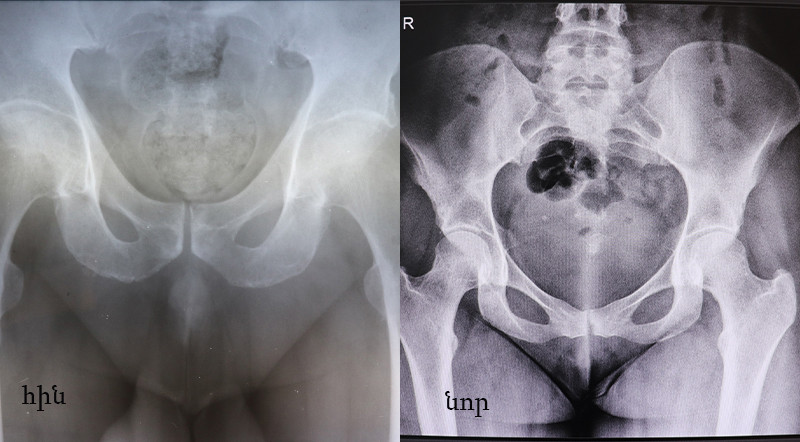

Ուռուցքաբանության ազգային կենտրոնի նոր ձեռքբերումներից մեկը՝ թվայնացնող սարքը հնարավորություն է տալիս ստանալ բարձր որակով ռենտգեն պատկերներ։

Թվայնացված և չթվայնացված ռենտգեն պատկերների որակական տարբերությունը հստակ երևում է ստորև բերված նկարներում։